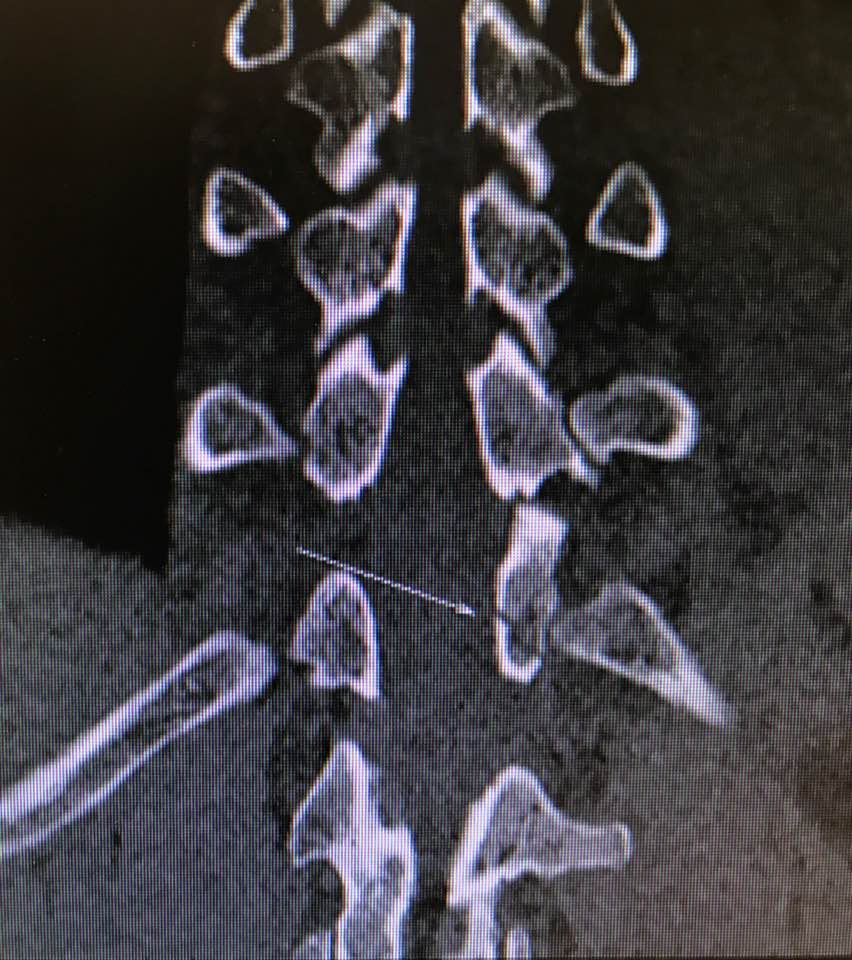

嚴重的工業意外受傷,T12胸脊椎不穩定的3段(前、中、後柱列)壓迫性脊柱椎體骨折

1. 即使您的胸部及胸脊椎柱被8英尺高和200磅重的巨大雪櫃嚴重壓碎, 您仍然生存, 您的中樞脊髓神經但沒有受到傷害.

2. 即使公立醫院忽畧了你不穩定的前、中、後3柱列的T12胸脊椎骨折,並在3天後容許你出院送回家, 你到私家醫院再進行第二次詳細檢查!

3. 幸運的是,入院前及兩天來你未有因為不穩定的脊柱椎體骨折碎片的移位而導致你脊髓中樞神經到不可逆轉和永久性的損傷致雙腿癱瘓及大小便失禁. 今天所有穩定你碎裂脊椎的手術都做完了.